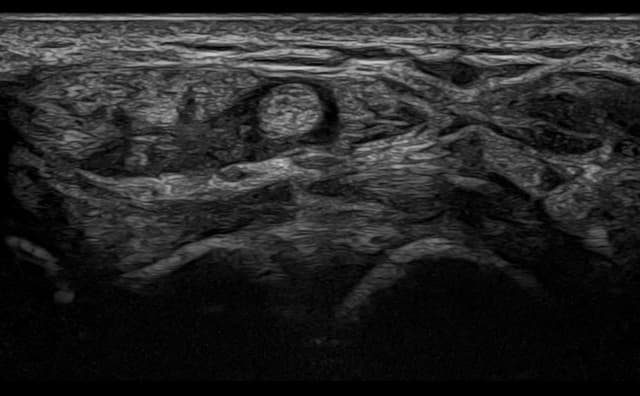

Mimics real human structures, allowing for precise needle placement and guided interventions.

Enables clear visualization of anatomical landmarks, needle movements, and injection sites.

Hands-on Interventional Training – Introducing simulator-based hands-on interventional training. These are one-of-a-kind and replicate human anatomy, allowing users to perform injections under ultrasound guidance like performing real-world procedures.